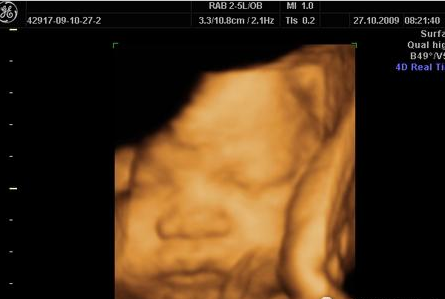

现在很多准妈妈通过各种宣传都知道了有一种神奇的技术叫做“四维彩超”,它能够让准妈妈实现给宝宝拍摄“零岁写真”的愿望。但是什么时候做四维彩超才是最好的时间?...

告诉我,你们选择了四维彩超吗?在选择之前,准妈们真的有做好功课吗?相信每个准妈说起彩超排畸都可以说得头头是道,但对于四维彩超的“真面目”你们到底了解多少?...

二维彩超,三维彩超,四维彩超……相信每个准妈妈准爸爸对这些孕期检查项目都不陌生。因为在孕20~24周时,医生们都会提醒妈妈们去做一个大排畸的检查。...